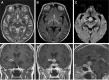

Background: Secondary central nervous system lymphoma (SCNSL) is a rare and aggressive disease, which is defined as secondary central nervous system (CNS) involvement in patients with systemic lymphoma. According to previous reports, SCNSL presents mostly with leptomeningeal spread; however, our experience differs. In the present study, we demonstrate the diversity of magnetic resonance imaging (MRI) patterns in SCNSL.

Patients and methods: Initial morphological MRI findings in 21 patients (10 women and 11 men with mean age 62.3±16.2 years) with SCNSL were retrospectively evaluated. All patients suffered from neurological symptoms and underwent MRI, and all cases were histologically verified. Twelve patients were treated by corticosteroids at the time of the initial MRI.

Results: Parenchymal lesions were present in 18 of 21 cases (85.7%), solitary meningeal infiltration was present in 1 patient (4.8%), leptomeningeal infiltration in combination with hypophyseal involvement in 1 patient (4.8%), and solitary involvement of the sixth cranial nerve (CN) was found in 1 patient (4.8%). Multiple lesions were present in 11 of 21 cases (52.4%). Diffusion restriction in all or part of the lesion was detected in 14 of 18 cases (77.8%). All parenchymal lesions had an infiltrative appearance and most enhanced homogenously (11 of 17 cases; 64.7%). A combination of parenchymal and meningeal involvement was found in 10 of 21 cases (47.6%). Infiltration of the CNs, basal ganglia, corpus callosum, and ependyma was present in 8 of 21 cases (38.1%) for each of the abovementioned structures; hypothalamic-hypophyseal axis was affected in 7 of 21 cases (33.3%).

Conclusion: In contrast to previous reports, SCNSL presented as parenchymal disease. MRI is not sufficient for differentiation between primary and secondary CNS lymphoma.